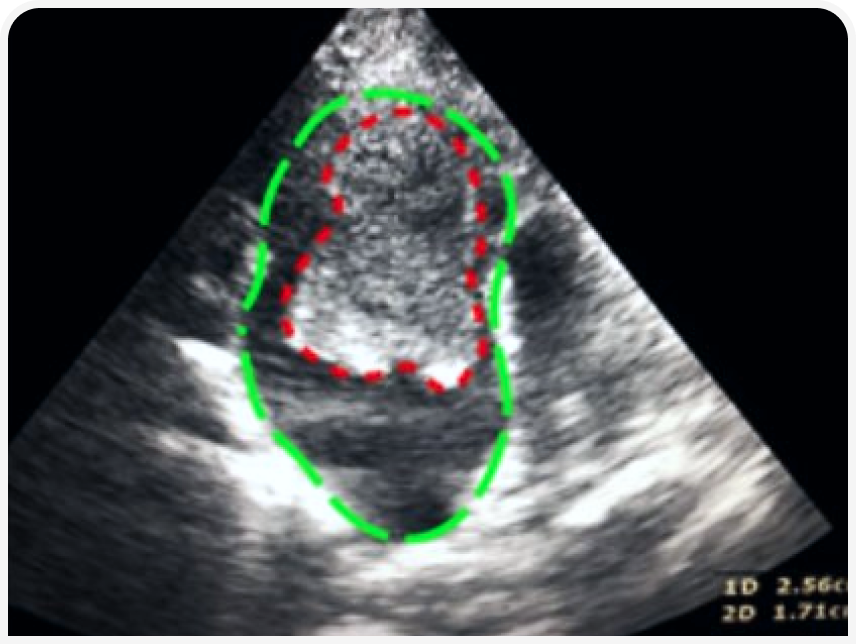

Эхокардиография (рис. 3–5). Данный метод позволяет выявить основное заболевание сердца. Также можно выявить изменение кровотока и замедленное прохождение крови в ушке или в полости левого предсердия посредством импульсно-волнового доплера. У некоторых кошек тромб, формирующийся (в виде облака) или зрелый, можно увидеть в левом предсердии.

УЗИ-скрининг брюшной полости для определения границ аортального поток. Аортальный кровоток можно визуализировать с помощью цветового доплера. Аорта визуализируется дорсальнее мочевого пузыря (рис. 6).